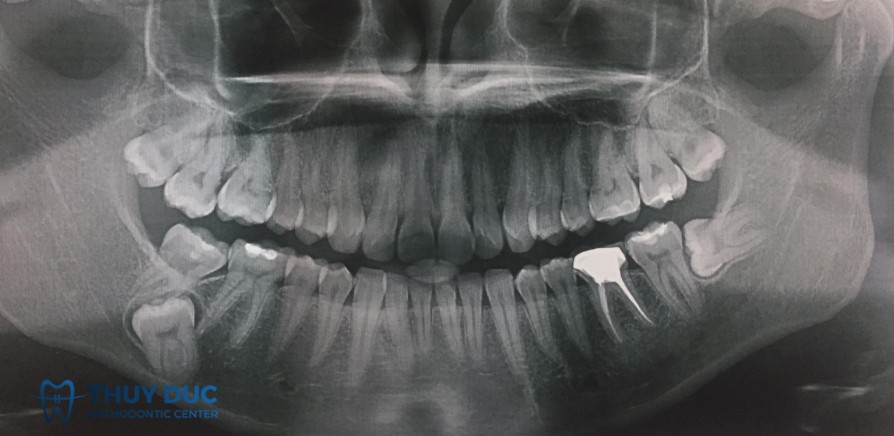

Tổn thương răng kế cận

Khi răng khôn mọc lệch, mọc ngầm hoặc sát răng kế bên, thao tác nhổ có thể làm tổn thương chân răng hoặc phá hủy xương quanh răng kế cận. Nghiên cứu ghi nhận khoảng 30% răng khôn ngầm có thể tác động tới răng bên cạnh, dẫn đến răng yếu, ê buốt hoặc tăng nguy cơ sâu răng, thậm chí phải điều trị tủy sau này.

- Vị trí và hướng mọc của răng khôn: Những răng mọc lệch, nghiêng, ngầm hoặc nằm sát ống thần kinh dưới hàm hoặc sâu trong xương làm phẫu thuật khó hơn và tăng nguy cơ tổn thương dây thần kinh, chảy máu hoặc các biến chứng khác.